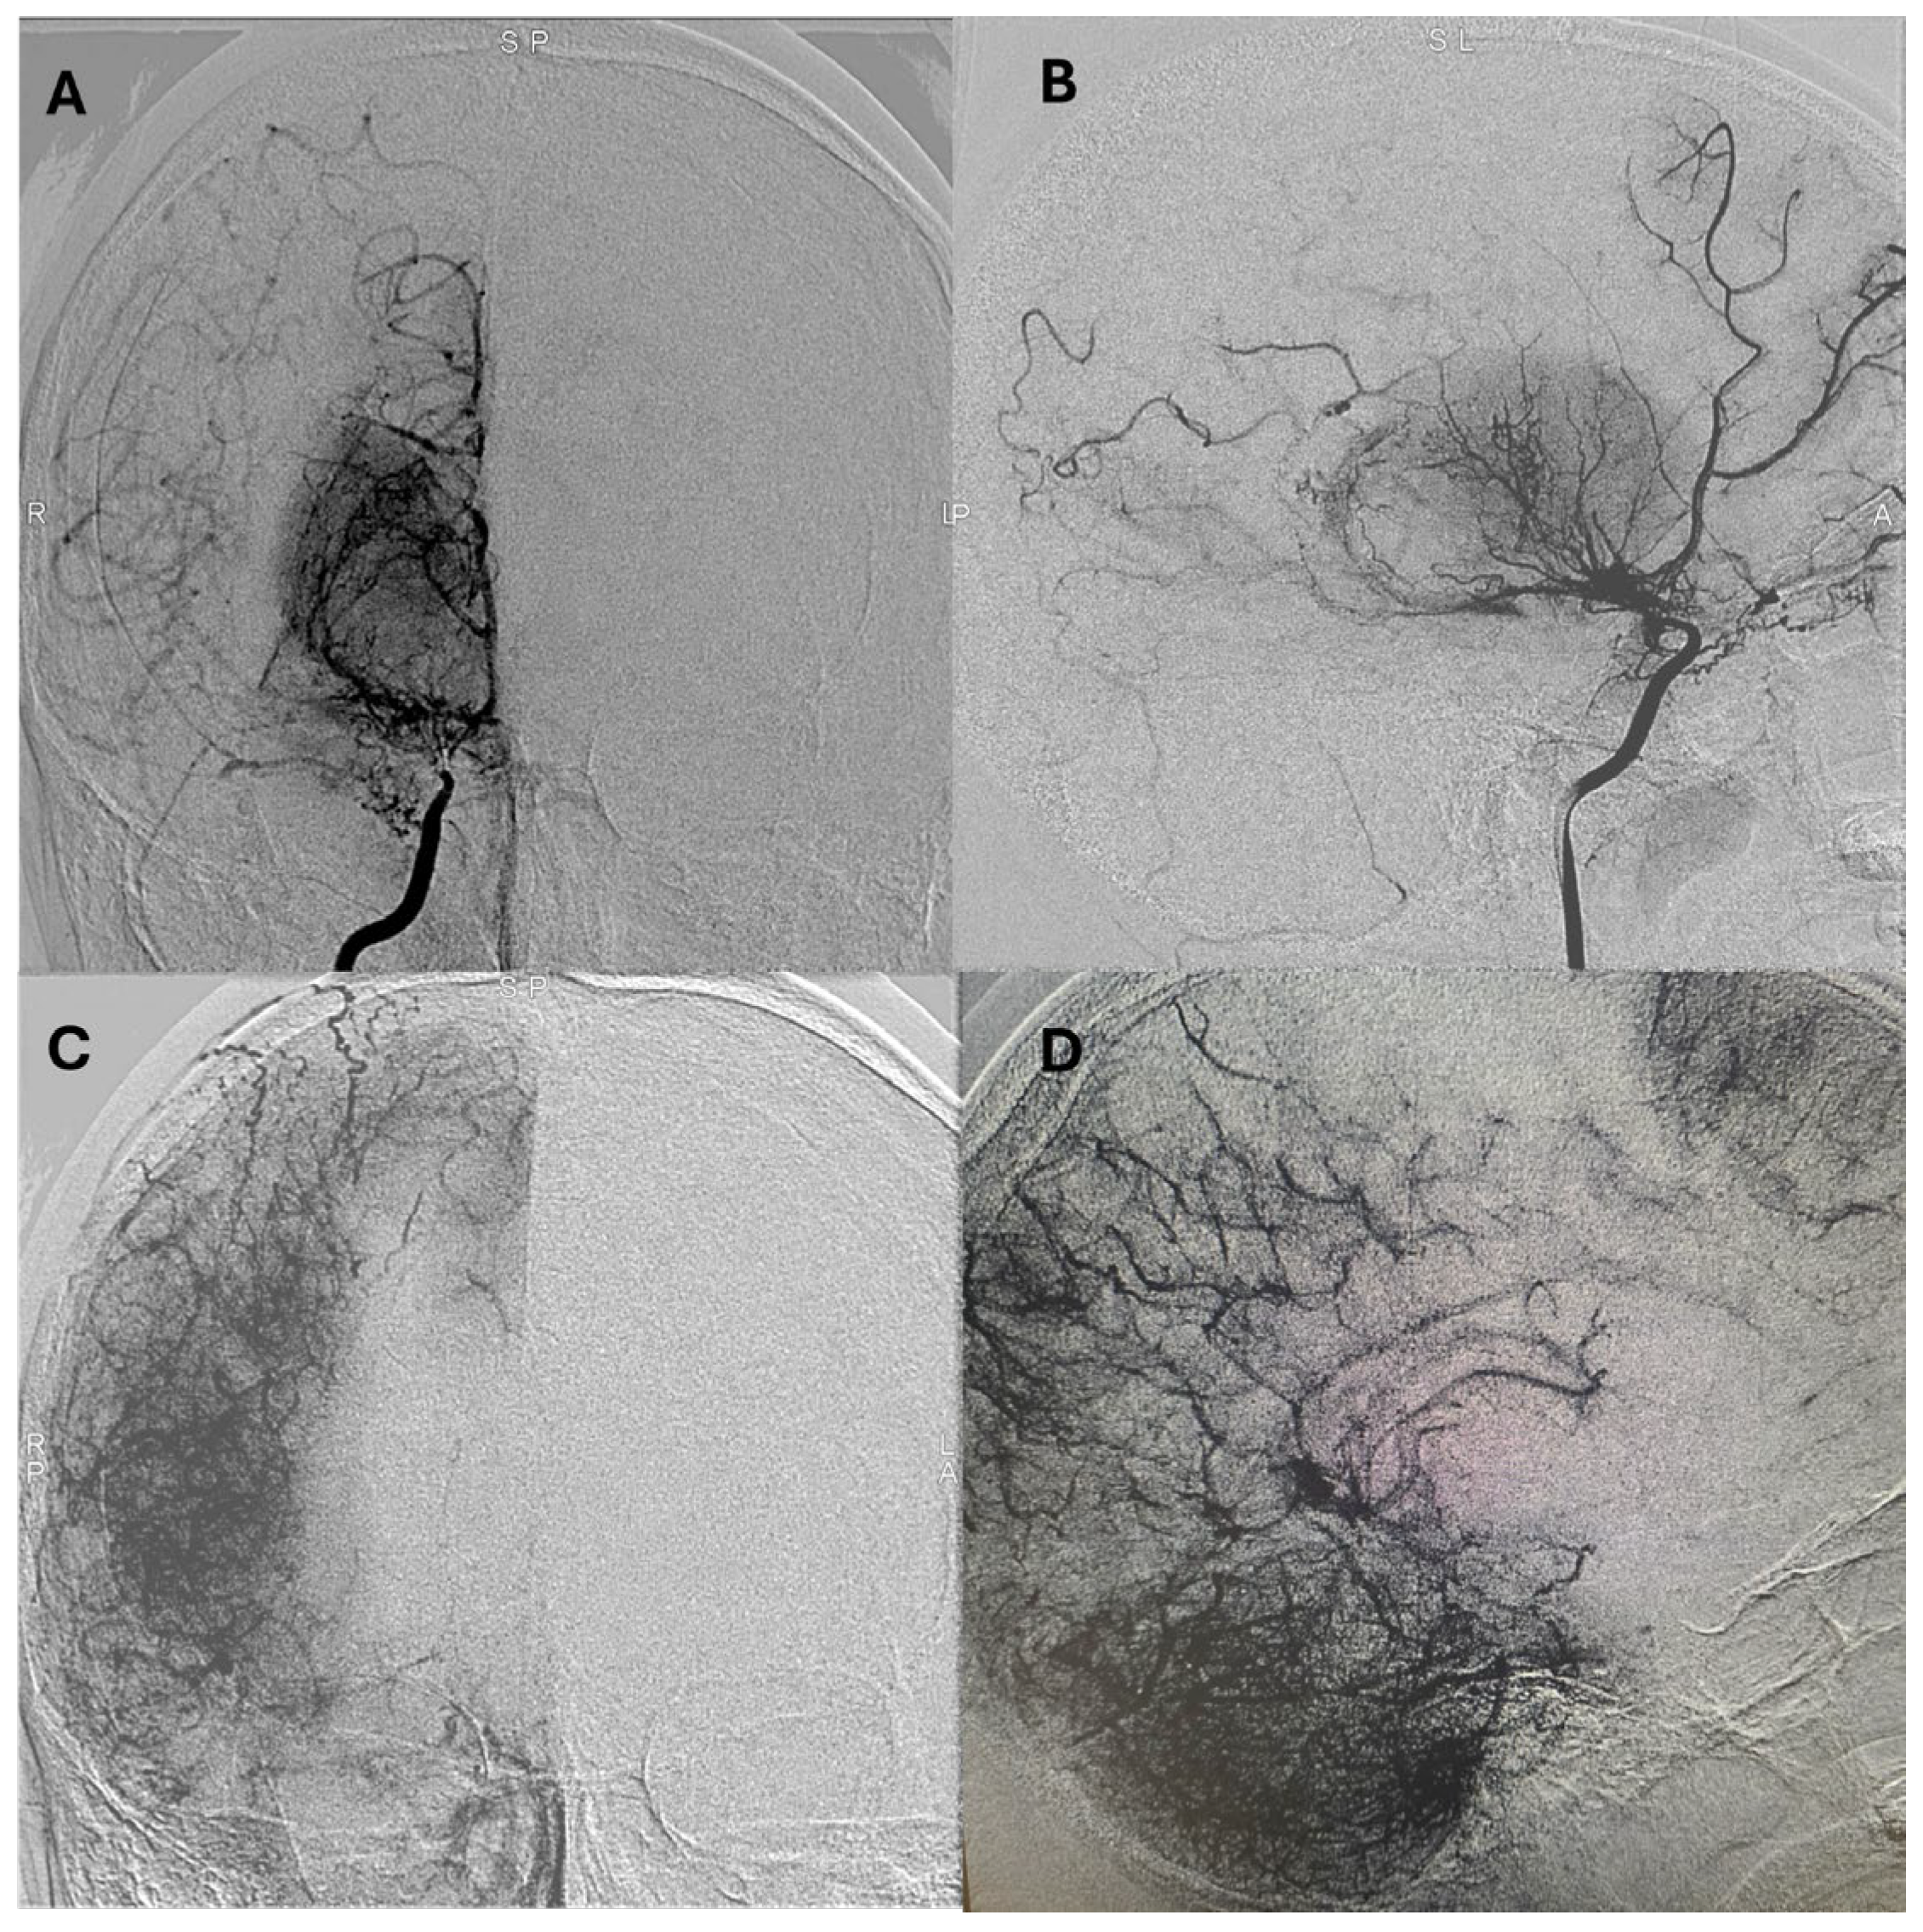

Representative postoperative angiographic images are shown in

Figure 1,

Figure 2 and

Figure 3. The mean operative time was 3.2 h and the average length of hospital stay was 7 days. All patients were monitored in the pediatric intensive care unit for 24–48 h before being transferred to the ward.

Postoperative angiographic follow-up was available for all revascularized hemispheres (n = 14). Examinations were typically performed at 3–6 months after surgery and repeated at 12–18 months in selected cases with persistent or recurrent symptoms. According to the Matsushima grading system, six hemispheres (43%) achieved grade A and 8 (57%) grade B collateralization, with no cases classified as grade C. Patients who developed grade A/B collaterals demonstrated parallel improvement in functional outcomes, with a median postoperative mRS of 1 compared to 2 preoperatively. Although the sample size precluded formal correlation testing, this qualitative relationship reinforces the functional impact of successful indirect revascularization on cerebral perfusion and recovery.